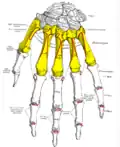

_01_palmar_view_with_label.png) Metacarpals shown in red. Left hand, anterior (palmar) view. | |

Metacarpus (yellow). Insertions are shown in red. Left hand, anterior (palmar) view.

Metacarpus (yellow). Insertions are shown in red. Left hand, anterior (palmar) view. -

Metacarpus (yellow). Insertions are shown in red. Left hand, posterior (dorsal) view.

Metacarpus (yellow). Insertions are shown in red. Left hand, posterior (dorsal) view.